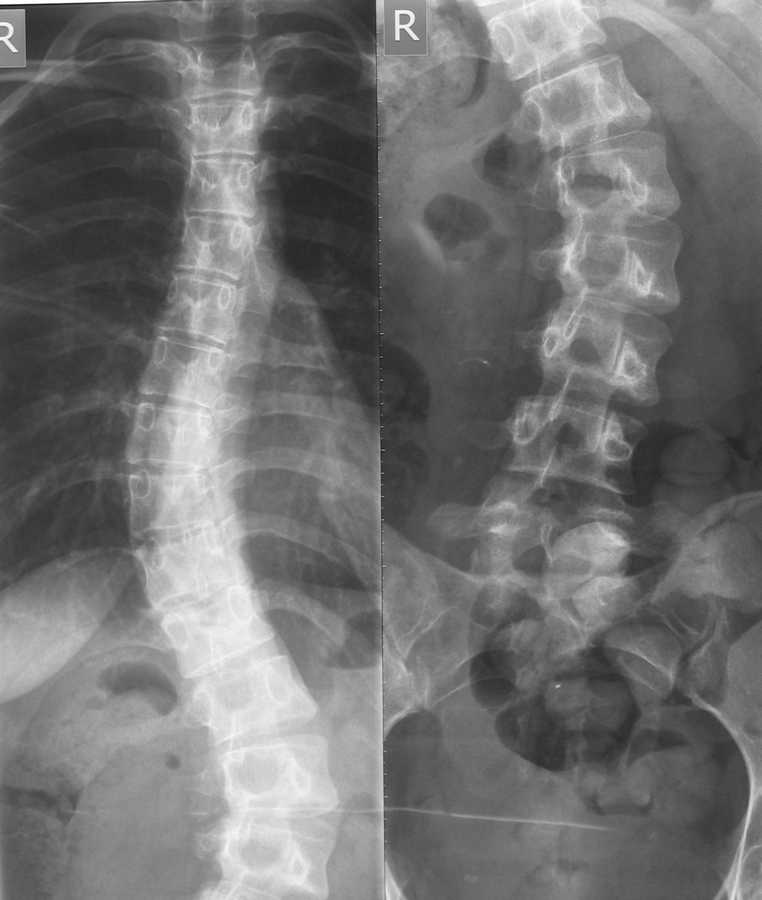

Здравствуйте уважаемые коллеги. Помогите разобраться в ситуации. Девушка 22 года, впервые выявлен сколиоз около 5 лет назад. Получала несколько раз курс

консервативного лечения. На данный момент ситуация видна на представленном

снимке. Клинически проявляется только в косметическом дефекте, боли не беспокоят. имеет ли смысл устранять косметический дефект хирургически,если - да, то на какой базе?